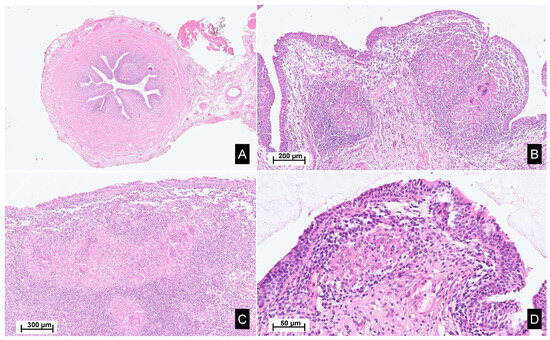

| Kidney involvement | Rarely described. Tubulointerstitial nephritis (rarely granulomatous), nephrocalcinosis and lithiasis | 2 to 10%: mainly nephrocalcinosis, renal stones. Granulomatous TIN in 20% (rarely alone) |